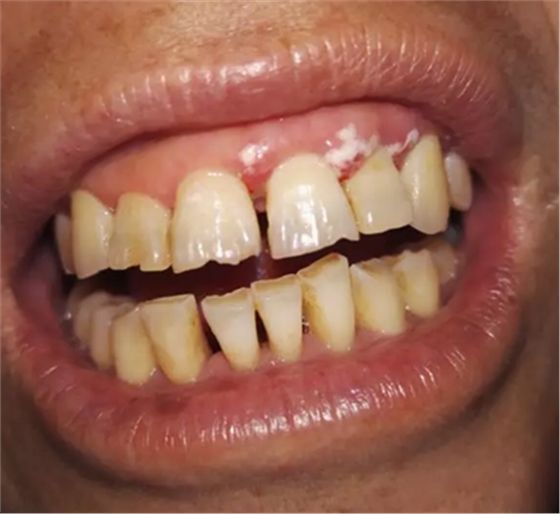

處置:首先進(jìn)行常規(guī)的牙周刮治,治療效果已經(jīng)很明顯,見(jiàn)圖片。